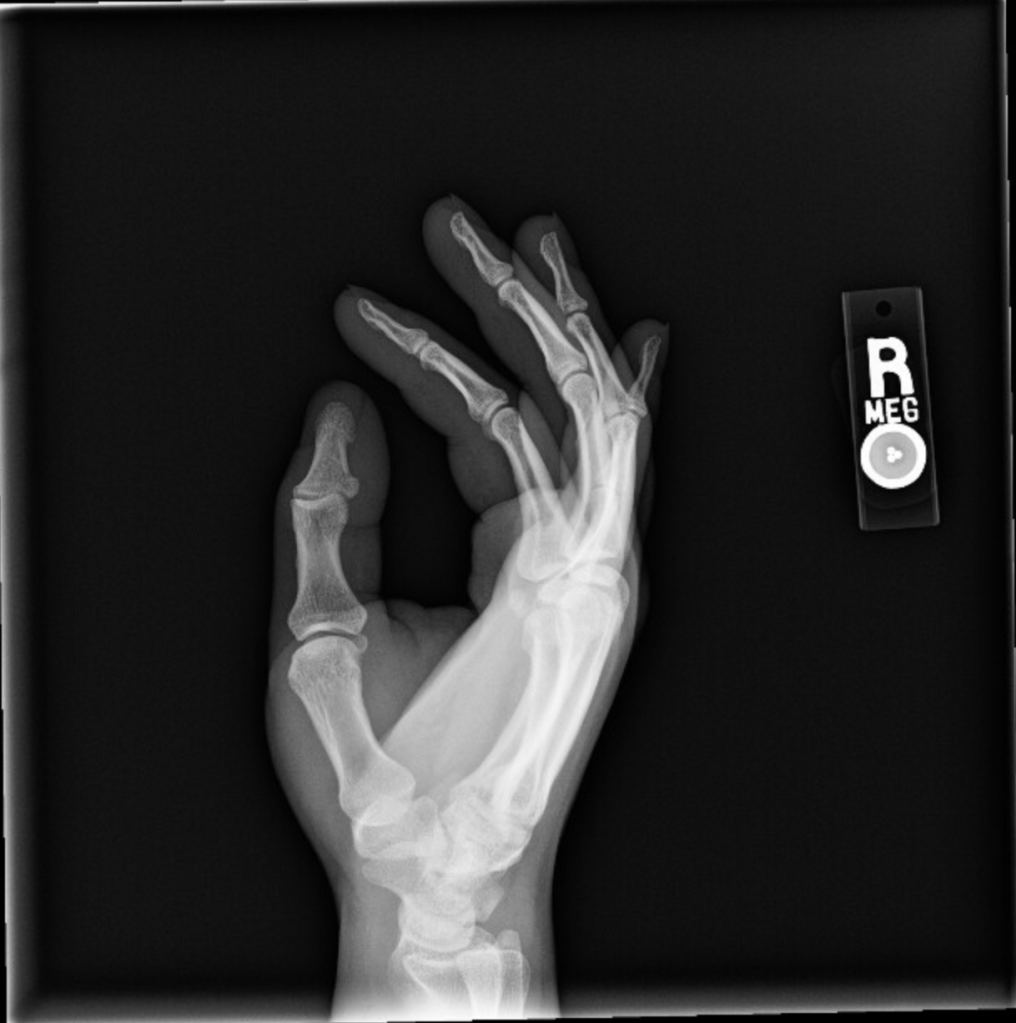

The reason I injured my wristโresulting first in probable tendonitis that made it basically impossible to use my right hand and then some mysterious secondary condition(s) that initially meant my left arm got really sore really easily and now is more of a joint thing that’s affecting both my hands and, to a lesser extent, all of my joints, but is probably not arthritis based on preliminary blood tests (my doctor thinks it’s carpal tunnel, but the test for that is booked until June)โis definitely not at all embarrassing, not at all something that I had advance warning of and could have easily avoided if I’d just listened to what my body was telling me, definitely don’t click that arrow.

I wake up in the morning with an odd discomfort in my right pinkyโwhen I unbend it, I get this weird kind of clicking feeling at the base. It's a little distressing but goes away after about an hour, so I ignore it. And sure my wrist hurts from all the tiny handwriting...and the several hours of Elden Ring and/or Need For Speed Unbound I play in between writing sessions, but I keep stretching it out and figure that's good enough. And I keep on that way through Friday as wellโafter waking up with the same weird pinky issue. Which I also have Saturday morning.

At this point I'm pretty sure something's going on, so I scale things back, but it's not until I wake up on Sunday feeling downright sore that I put a stop to all nonessential wrist functions. I call out of work, take the day to rest, go to bed early, and figure I'll feel basically fine tomorrow.

At approximately 11:30 pm I wake up and can't move the fingers on my right hand.

So April 3rd is my first appointment with the hand specialist. My assumption for how this is going to go is that I’m going to explain my symptoms and he’s going to say, “Yeah, that’s pretty standard for this kind of injury, here’s some sort of medication or some other specific treatment and a referral for physical therapy.” That is not what happened. After I explained my symptoms he had me do all these movements with my hands that the urgent care physician had had me do and had then told me that I definitely didn’t have carpal tunnel, and so of course the hand specialist tells me he thinks it’s carpal tunnel. “So the test for that is a nerve conduction study, those usually take a while to open up so we’ll try to get that process started as soon as possible, and in the meantime we can run some more blood tests just to rule out arthritis.” “How long is a while?” “Probably two months.”

- It has, at time of writing, been 13 weeks. My nerve study is in 4 days. My next doctor’s appointment to discuss the results is in a week. My hands are still hurting.